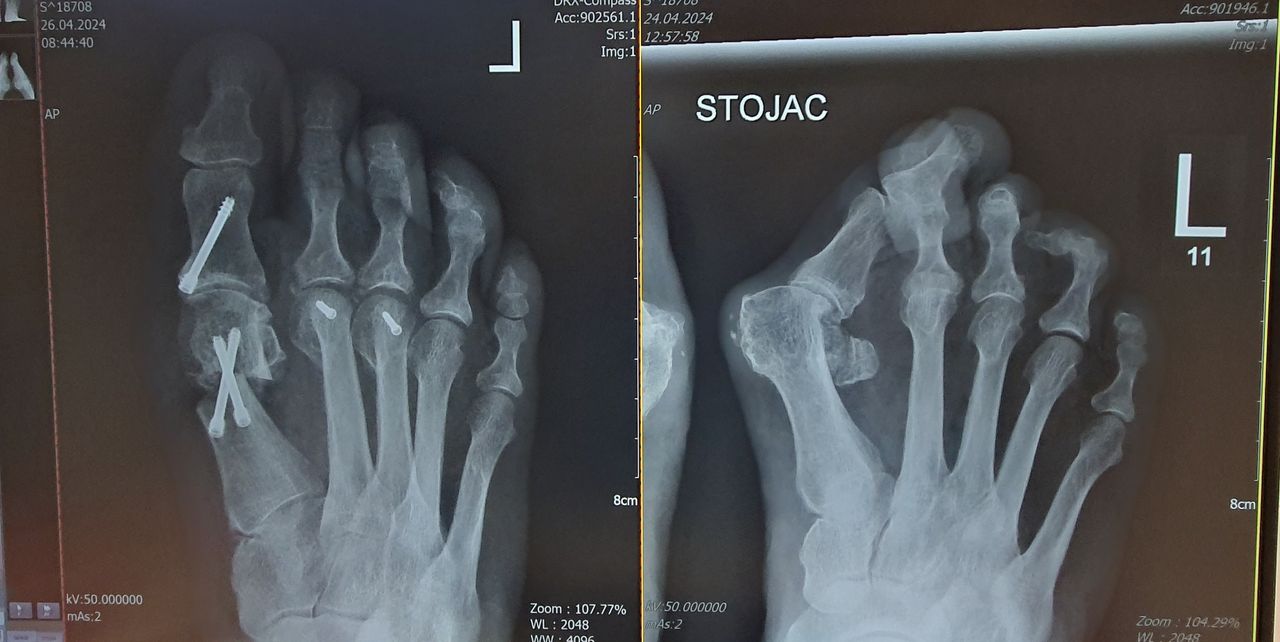

Zdjęcia i filmy